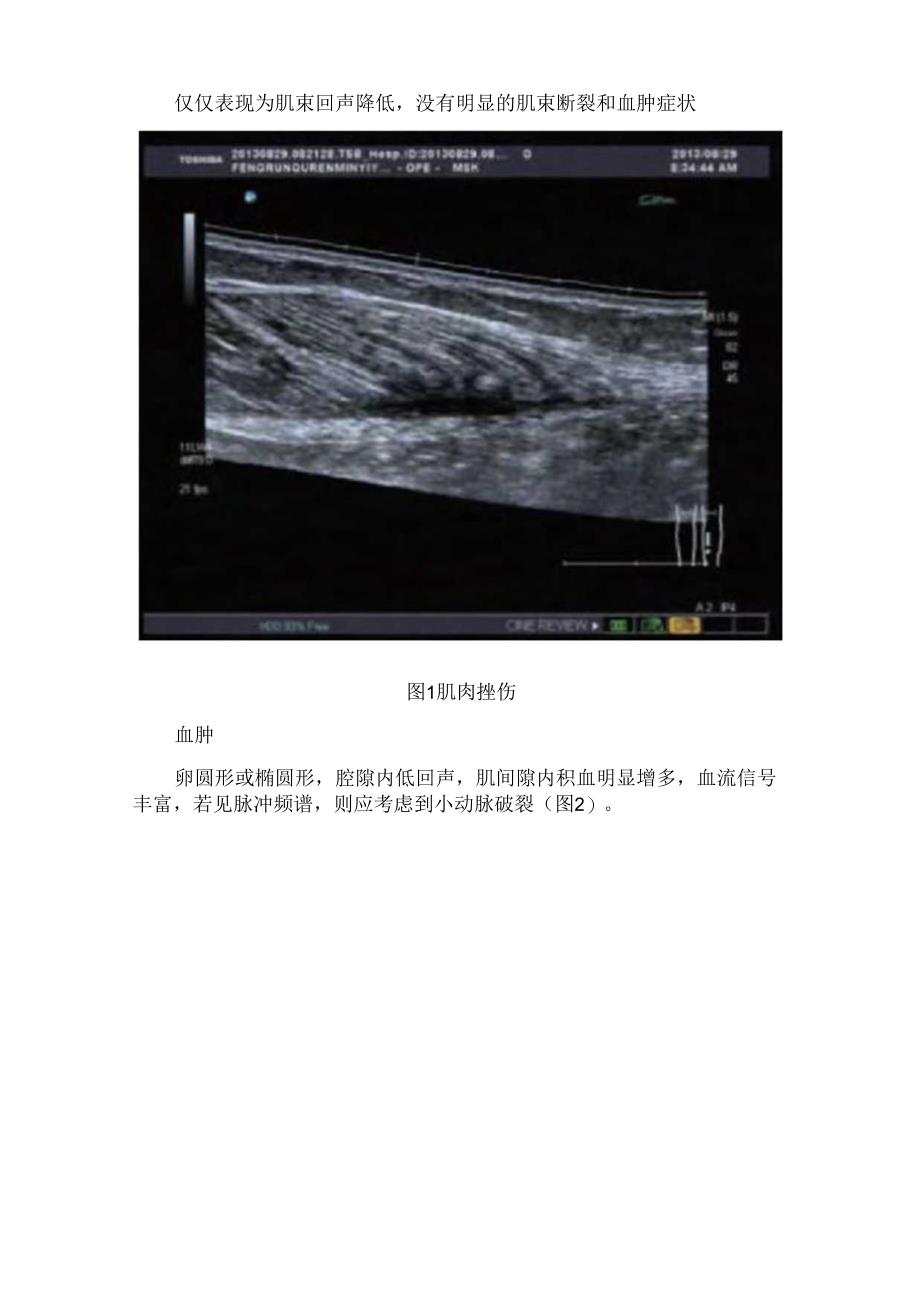

3、而肌肉损伤在临床上可分为肌肉挫伤、血肿、肌肉撕裂及肌疝。肌肉挫伤仅仅表现为肌束回声降低,没有明显的肌束断裂和血肿症状图1肌肉挫伤血肿卵圆形或椭圆形,腔隙内低回声,肌间隙内积血明显增多,血流信号丰富,若见脉冲频谱,则应考虑到小动脉破裂(图2)。图2血肿肌肉撕裂肌肉组织局部连续性中断、肌纹理不够清晰、周边肌肉组织发生肿胀,肌肉内可发现类梭样或者不规则肿块回声;若完全撕裂,图像显示肌肉连续性完全中断,而且边缘毛糙,肌肉断端回缩较为明显,局部形成肿块样组织,容易出现血肿而导致空腔(图3)。图3肌肉撕裂肌疝。较为少见,表现为局部肌肉外凸,包绕肌肉筋膜组织出现局部撕裂,而肌束未见明显撕裂(图4)。图4肌疝高频彩超多普勒超声在对血肿、肌肉断裂、肌肉挫伤、肌疝等肌肉损伤病症进行诊断时,其诊断精确率较高,而且患者的病程时间越长,其超声呈现则不典型,诊断精确率相对低下,而年龄越大患者的肌肉组织损伤越显著,凸显其较高地诊断精确率